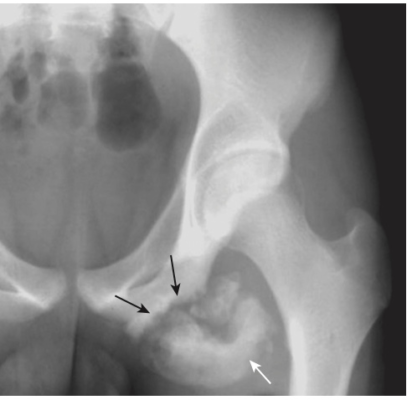

Gãy cổ xương đùi ở người già

- Thường gặp và thường liên quan đến loãng xương

- Chụp X quang cổ xương đùi thường quy nên được thực hiện với chân của bệnh nhân ở tư thế xoay trong để hiển thị cổ ở dạng trực diện. Tìm dấu gập góc của vỏ xương hoặc các vùng có tăng đậm độ chứng tỏ có sự chồng lấn (Hình 19).

- Đôi khi gãy cổ xương đùi có thể rất khó nhận biết và cần phải chụp MRI hoặc scan xương bằng phóng xạ hạt nhân để chẩn đoán.